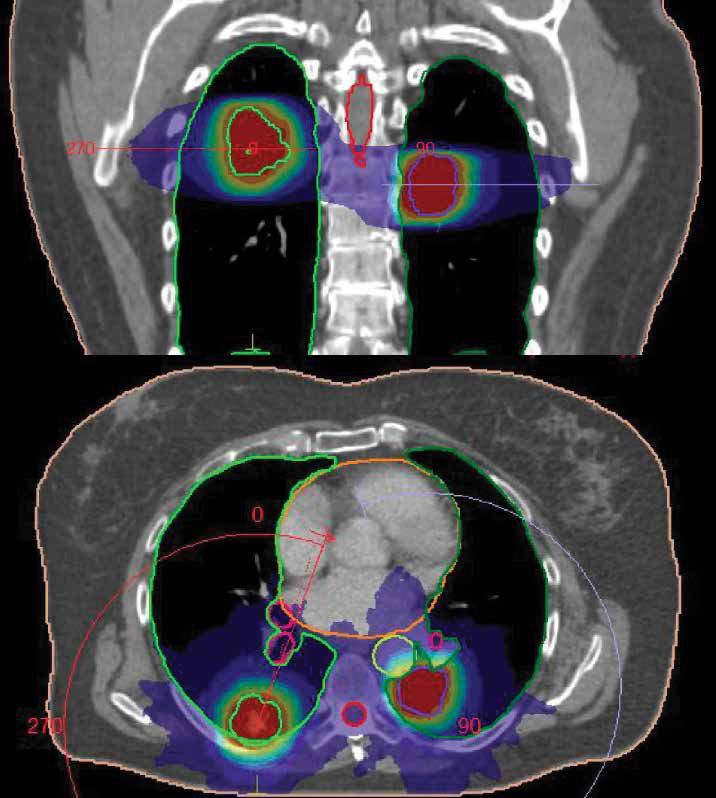

VMAT is an advanced radiation therapy approach that leverages the rotating capability of the LINAC (linear accelerator) machine to deliver radiation with exceptional precision and significantly shorter treatment times. VMAT is employed effectively in the management of various cancer types, including brain, breast, cervical, colorectal, oesophageal, lung, and nasopharyngeal cancer.

VMAT combines rotational and modulated techniques. As the LINAC gantry rotates around the patient, the radiation beam's shape and intensity are continuously adjusted to match the tumour's contours. This dynamic modulation ensures that the optimal radiation dose is delivered to the tumour while minimising exposure to healthy tissues, making VMAT more precise and targeted than conventional approaches.

Can be used for tumours of various sizes and locations throughout the body.

VMAT can be used with conventional fractionation (15 to 35 fractions) or hypofractionation, depending on the clinical scenario and the prescribed dose.

Administers radiation in smaller, more controlled doses during each session.